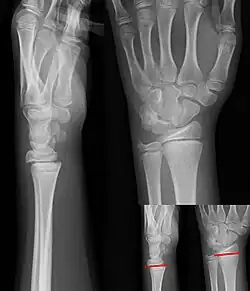

Salter–Harris I fracture of distal radius. -